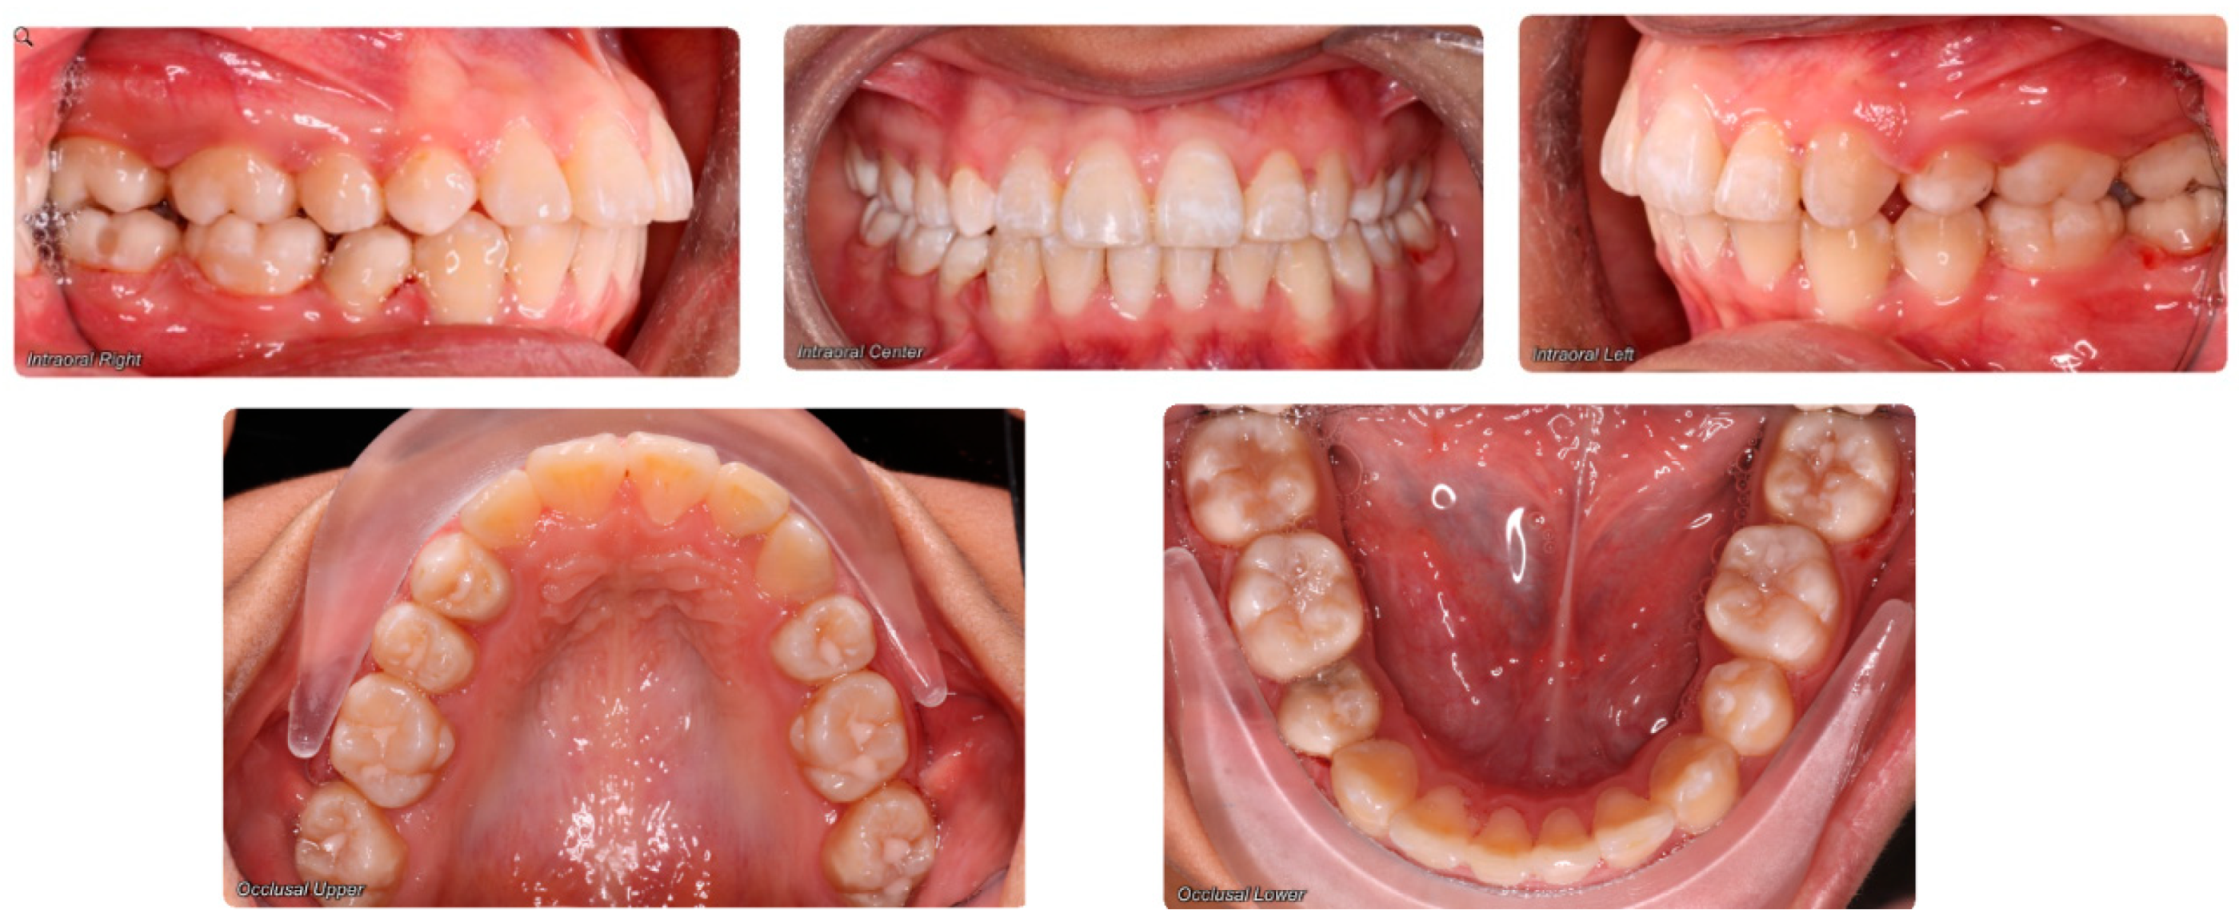

- Assessment of an impacted canine with close proximity to the lateral incisor. Figure 27 shows photographs and a panoramic radiograph of a case in which there is an impacted permanent maxillary right canine in an unfavorable position, a missing mandibular left second premolar and uncoordinated dental midlines. The relationship of the impacted canine to the adjacent lateral incisor cannot be determined from the conventional 2D radiograph. Therefore, CBCT was acquired. Figure 28 shows CBCT images, including coronal, sagittal, axial views, and volume rendering, which demonstrated close proximity of the impacted canine to the lateral incisor, and an area of bone loss buccal to the crown of the impacted canine. Before acquisition of CBCT, the tentative treatment plan was to extract the maxillary right first premolar and bring the canine to the dental arch. However, due to the findings presented by CBCT, the treatment plan was altered in favor of extracting the impacted canine, a clinical decision that was strongly favored by the patient. In this case, the first premolar would substitute for the canine. The maxillary left first premolar and mandibular right first premolar were also extracted. Therefore, each quadrant would have one missing tooth by end of treatment. Orthodontic post-treatment photographs are presented in Figure 29. Figure 30 shows a post-treatment 2D panoramic radiograph. CBCT was neither necessary nor indicated at completion of orthodontic treatment, and therefore only a conventional 2D panoramic radiograph was taken.